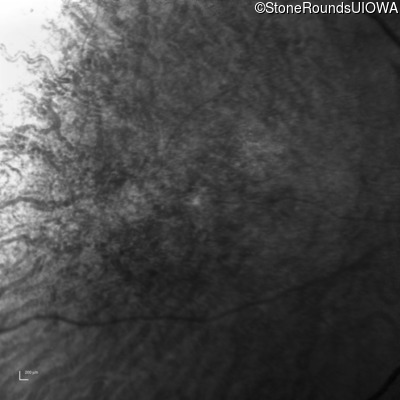

Age at visit: 41 years

This 41 year old man first came to medical attention at age 18 months when exotropia and amblyopia of his right eye were discovered. At age 11 vitreous strands and retinal vascular sheathing were seen. He has had poor night vision and constricted visual fields since his late teens. Later, at age 44 a traction retinal detachment was noted in his left eye and was treated with a scleral buckle.